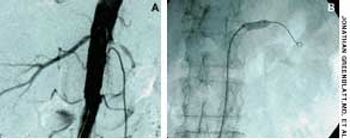

Police brought a delirious, combative 24-year-old man to the emergency department. The patient was unable to provide any history on arrival, but his scarred, blistering lips and his vital signs (blood pressure, 166/102 mm Hg; heart rate, 97 beats per minute; respiratory rate, 24 breaths per minute; and temperature, 38.2°C, or 100.9°F) led to a possible diagnosis of cocaine-induced delirium.